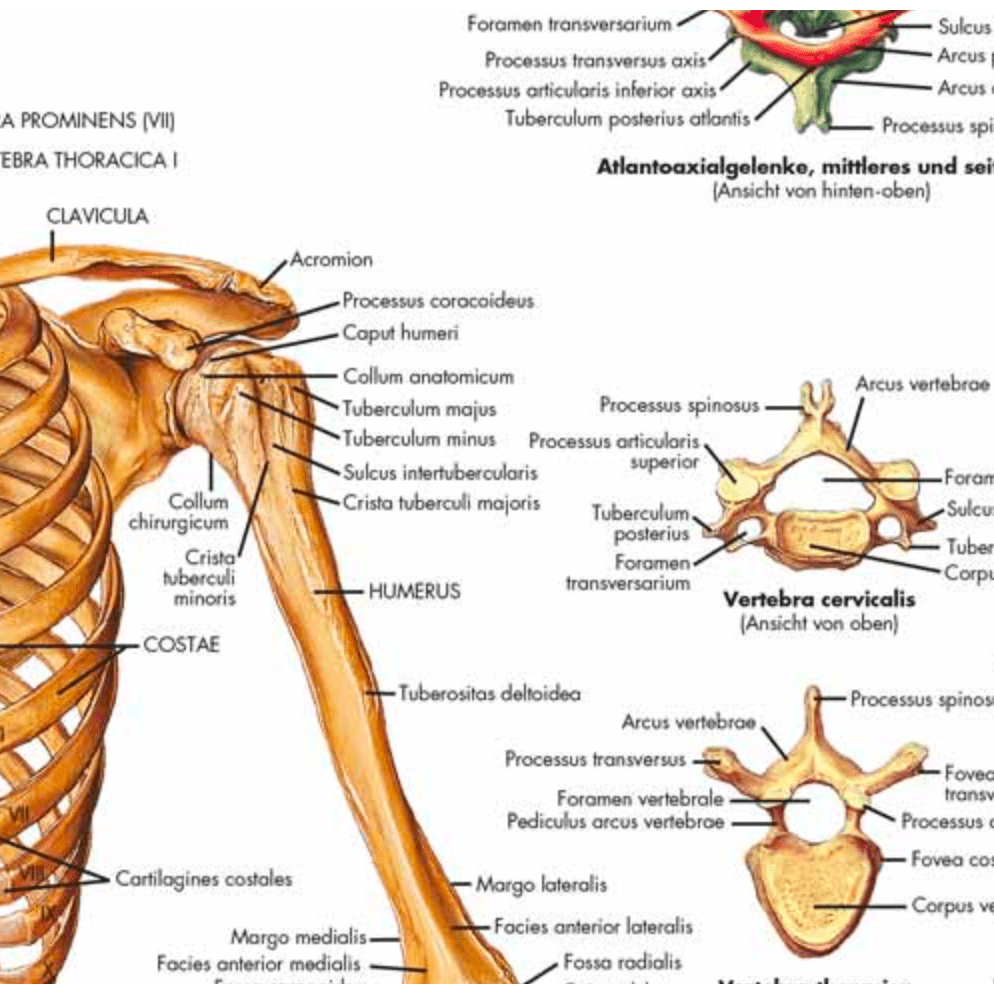

Muscle posters

Muscles provide movement to the musculoskeletal system, and their origins, insertions and lodges are clinically important for every healthcare professional. That is why we at eAnatomi have both developed and designed our own anatomy posters, which provide the ultimate overview of all the muscles of the body. On this page you can find both our own posters and posters from other manufacturers. We offer posters in several different languages such as pure Latin, Danish, English and Swedish, etc.